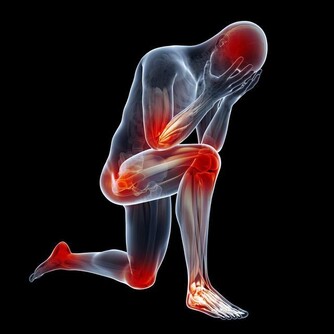

半夜小腿抽筋,發作時疼痛難忍,往往把人痛醒,有好長時間不能止痛,且影響睡眠。

那麼,怎麼才能在抽筋時,快速消除抽筋呢?一般人會捏捏腿肚子、扳扳腳趾:

腿抽筋原因有很多,最常見的是寒冷刺激,另外還有缺鈣、運動不當等。